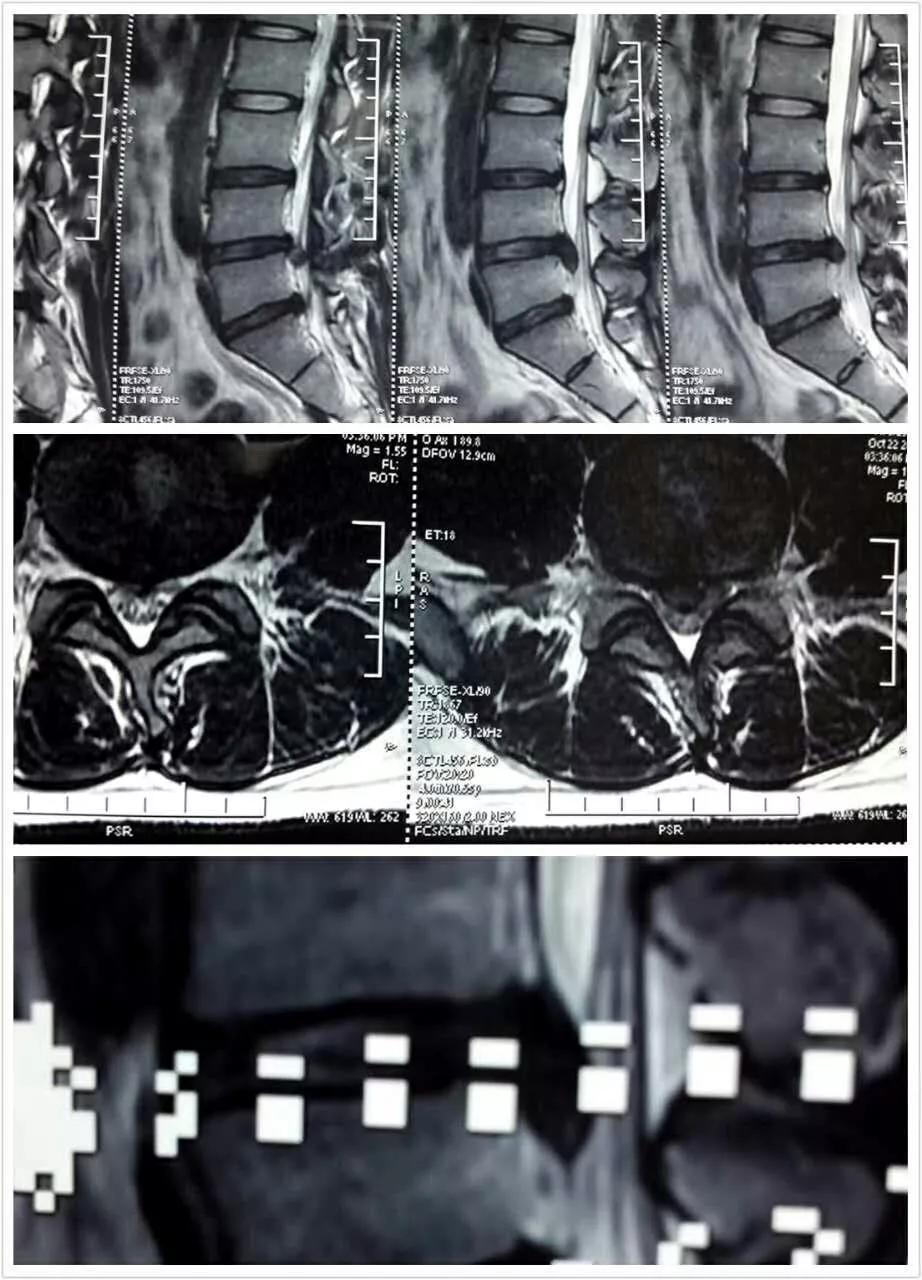

对于保守治疗无效,腰椎滑脱进行性加重,或者滑脱致椎管狭窄、神经受压严重的患者则需要尽早手术治疗。手术治疗的目的主要有以下三个方面

解除神经压迫——“减压”;

利用内固定器械复位滑脱椎体——“复位”;

实现滑脱椎体与相邻椎体的骨性融合——“稳定”

与开放性手术比较,微创经椎间孔入路的椎间融合术具有组织损伤小、术中术后出血少、术后疼痛轻恢复快、减少住院时间等优点,但手术难度大,对医生的手术技巧要求高。